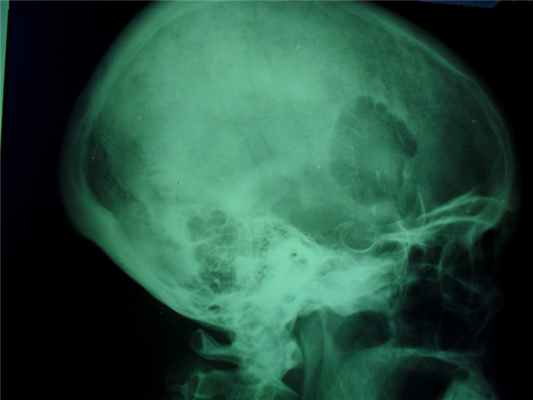

Различают губчатую остеому, остеому, состоящую из коркового и губчатого вещества, и остеому из сплошного компактного вещества. Первые два вида наблюдаются на длинных трубчатых костях, компактные остеомы поражают плоские кости черепа.

Рентгенодиагностика компактной остеомы:

- округлая, шаровидная или яйцевидная форма,

- опухоль дает гомогенную бесструктурную тень.

При локализации гемангиомы в плоских костях свода черепа происходит:

- вздутие кости и разрушение коркового слоя, надкостница приподнимается опухолью,

- характерен структурный рисунок – из центра опухоли к ее поверхности лучеобразно или веерообразно рассыпаются тонкие и более грубые костные балки.